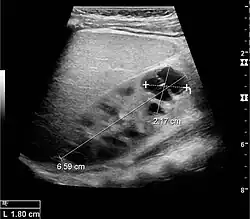

Figure 8. Cortical solid mass, which later was shown to be renal cell carcinoma. Measurement of the solid mass on the US image is illustrated by '+' and a dashed line.[1]

Figure 9. Renal cell carcinoma with both cystic and solid components located in the cortex. Measurement of tumor on the US image is illustrated by '+' and a dashed line.[1]

A solid renal mass appears in the US exam with internal echoes, without the well-defined, smooth walls seen in cysts, often with Doppler signal, and is frequently malignant or has a high malignant potential. The most common malignant renal parenchymal tumor is renal cell carcinoma (RCC), which accounts for 86% of the malignancies in the kidney. RCCs are typically isoechoic and peripherally located in the parenchyma, but can be both hypo- and hyper-echoic and are found centrally in medulla or sinus. The lesions can be multifocal and have cystic elements due to necrosis, calcifications and be multifocal (Figure 8 and Figure 9). RCC is associated with von Hippel–Lindau disease, and with tuberous sclerosis, and US has been recommended as a tool for assessment and follow-up of renal masses in these patients.[1]